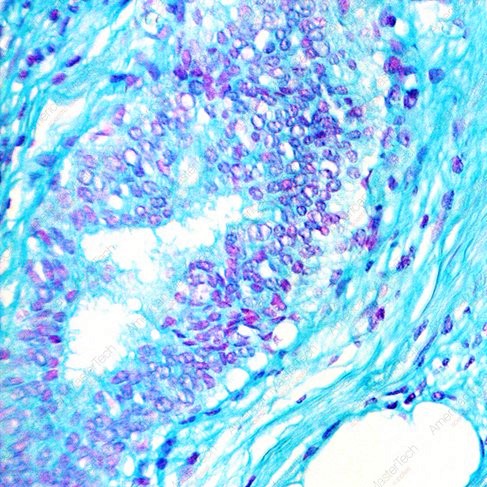

La metacromasia es un fenómeno en histología que se manifiesta como un cambio en la coloración de las muestras cuando se tiñen con colorantes específicos. Este cambio de color ocurre…

La metacromasia es un fenómeno en el que ciertos colorantes básicos reaccionan con los componentes del tejido y cambian su color normal de azul a rojo o púrpura. Este fenómeno…